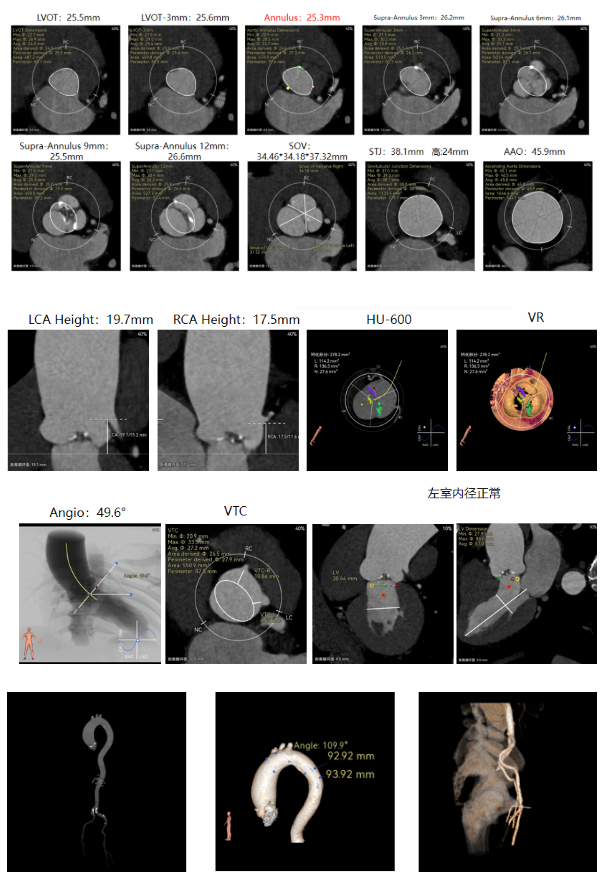

谷兴华教授 山东大学齐鲁医院 锚定终身获益,重视首次干预选择:心脏瓣膜病介入中心成立2年多来,中心核心目标始终保证在解决即刻病症的基础上,护航患者的全生命周期健康管理。 摆在眼前的实际是日益年轻化的患者群体,这意味着我们从手术伊始,就必须将患者未来数十年的生活质量和再次干预风险纳入核心考量,主动规划长远的健康路径。此次患者选择更具耐久的新型干瓣技术,力求减少患者未来再次干预的风险。同时,通过“TAVR+PCI一站式手术”这样的团队协作模式,系统性地处理多重心血管问题,避免分次手术的负担与风险,这正是我们中心一直秉持的“心脏瓣膜病全生命周期管理”理念的实践。让我们一起探索从“治已病”真正迈向“管长远”,让更多的患者获益! 病例特点速览 本次救治的患者,病情呈现“基础病交织、多病变叠加、锚定风险高”三大核心特征。患者为65岁,女性,病变特点TypeI型二叶瓣、轻度钙化,锚定风险大;同时患有冠状动脉粥样硬化性心脏病、慢阻肺(COPD);既往有长期吸烟饮酒史、脑梗死病史、高血压病史、乙肝小三阳病史及腹股沟疝修补手术史,患者STS评分9.32%,外科手术高危,经齐鲁医院瓣膜中心团队评估认为:局麻下“一站式TAVR+PCI”为最优治疗方案,结合患者较年轻,可选择具有长期耐久性的干瓣。 患者病史 主诉:活动后胸闷、憋喘余,加重20余天 既往史:30年前确诊乙肝小三阳,否认其他传染病史;有右腹股沟疝修补手术史,高血压病史,近期规律服药控制。 现病史:患者1年前出现活动后胸闷、憋喘,休息可缓解,为进一步诊治。2月前因“突发意识模糊、口齿不清”于当地医院入院,诊断为“急性脑梗死”,予以微创介入取栓治疗,恢复可,未遗留后遗症。20天前于当地医院再次入院行脑血管支架植入术,术后出现胸闷、憋喘,伴大汗,行心脏超声提示主动脉瓣重度狭窄,并行冠脉造影检查,予以药物治疗。10天前就诊于我院复查心脏超声提示二叶式主动脉瓣,主动脉瓣狭窄(重度)并反流(轻度)。患者现仍感胸闷,双上臂疼痛不适,咳嗽咳痰,日常活动受限。为行进一步治疗就诊于我院,门诊以“主动脉瓣狭窄、冠状动脉粥样硬化性心脏病”收入院; 个人史:吸烟50年,饮酒50年; 体格检查:体温:36℃,脉搏:67次/分,呼吸:18次/分,血压:143/76mmHg; 术前超声提示: 二叶式主动脉瓣主动脉瓣狭窄(重度)并反流(轻度);升主动脉扩张、左心扩大三尖瓣反流(少量);左室充盈异常;CW测最大压差86mmHg,平均压差43mmHg,最大血流速度463cm/s,连续方程法估测主动脉瓣口面积0.78cm² 术前CT评估 Type1型二叶瓣,轻度钙化、左右融合,主动脉瓣环径25.3mm,LVOT直径25.5mm,鱼嘴空间约26.6mm,主要靠瓣环锚定。窦部空间大、左右融合,VTC空间足够,无冠脉风险 ;左室内径正常,主动脉瓣环水平夹角49.6°。外周双侧入路内径可,髂外动脉存在散在钙化、双侧入路能够支持20F大鞘通过,右股低分叉,主动脉弓距弓角可。 个性化手术策略:局麻一站式方案+创新瓣膜精准适配 入路选择:主入路:右侧股动脉(右股分叉上方1cm处穿刺);辅入路:左侧股动脉;器械:20F大鞘; 手术流程规划:局麻下行同期一站式TAVR+PCI,植入ProStyle A®预装干瓣; 瓣膜选型与预处理:瓣膜型号:ProStyle A® AV32;不预扩; 定位与释放方案:初始定位:瓣上3mm处释放,瓣膜自然下滑至工作位,最终目标“0-瓣下5mm位”。 手术过程:局麻一站式操作+创新瓣膜植入,无缝衔接 手术团队按预设方案稳步推进,实现TAVR、PCI与ProStyle A®干瓣植入的无缝衔接: 1.术前准备:完成影像评估、血管通路建立,确认ProStyle A® AV32瓣膜状态; 2.PCI治疗:通过主入路完成左冠造影,前降支、对角支明显狭窄,精准植入两枚支架,恢复冠脉血供; 左冠造影,前降支、对角支病变 PCI后造影,病变血管充盈良好 3.主动脉根部造影:确认主动脉根部解剖结构,并精准跨瓣; 主动脉根部造影 精准跨瓣 4.干瓣植入:将瓣膜输送过弓、过瓣,并精准定位; 输送系统柔顺过弓 精准定位 5.术中评估:释放瓣膜至工作状态,再次造影评估,位置满意,完全释放瓣膜; 工作位评估 32号瓣膜稳定脱钩 6.释放后造影:可见瓣膜位置满意、形态良好,无明显瓣周漏。 最终造影,位置形态良好,无瓣周漏 术后超声探查:位置(瓣下4mm)、形态良好,无瓣周漏,PGmean=10mmHg。 此次手术的成功,体现了山东大学齐鲁医院心脏瓣膜病介入中心秉承的“心脏瓣膜病全生命周期管理”的理念和团队协作的临床能力。面对低龄高风险复杂病例,团队通过术前充分评估、术中精细操作,结合具有长期耐久性的干瓣技术,以一站式方案改善患者症状、提高生活质量并延长寿命,为类似病例的诊疗提供宝贵经验。 专家简介 谷兴华 山东大学齐鲁医院(点击查看专家详细简历)